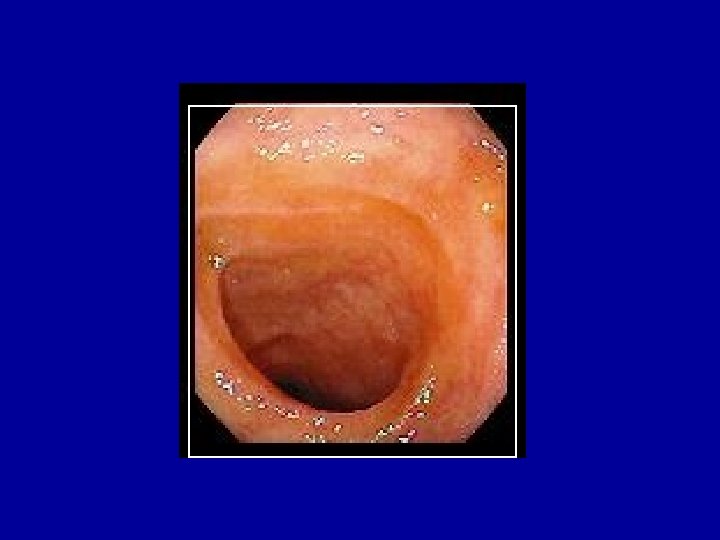

CÔLON (1)

CÔLON

CÔLON • Absorption colique (eau) : 4% • Stockage des matières fécales avant défécation provoquée par la distension du rectum par les selles • Fragmentation des selles • Production de gaz intestinaux (pullulation microbienne) • Poids des selles : 150 -300 g/j – 100 g d’eau – Déchets bactériens – Pigment biliaire marron : stercobiline • Contrôle anal volontaire et involontaire de la défécation (sphincters striés et lisses)